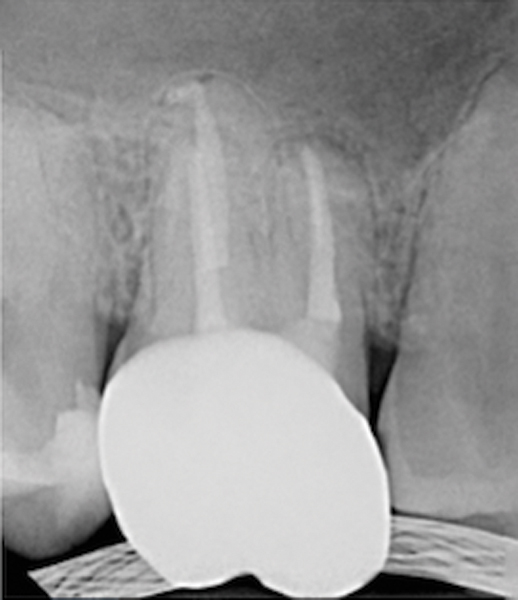

Figure 19. Preoperative radiograph of a case demonstrating apical periodontitis. Courtesy of Dr. Allen Ali Nasseh.

Figure 19

Figure 20. Immediate postoperative radiograph. Courtesy of Dr. Allen Ali Nasseh.

Figure 20

Figure 21. 5-year follow-up with complete healing. Courtesy of Dr. Allen Ali Nasseh.

Figure 21

This sealer solves most, if not all, of the previous problems of traditional sealers. Therefore, a thicker layer of sealer can be used because it is dimensionally stable and does not wash out. The core is used only as a hydraulic pump to move the sealer into place and allow for post space preparation or a pathway for retreatment. In addition and most importantly, the root canal preparation can be conservative and better adapted to restorative needs, since a traditional gutta-percha point (and not a metal plugger) is used to move the filling material. An additional benefit of the system is that there are now gutta-percha points that are impregnated with nano particles of bioceramics, so the sealer bonds not only to the root surface but also to the outer surface of the gutta-percha, eliminating the gap between the two (Figure 19 through Figure 21).